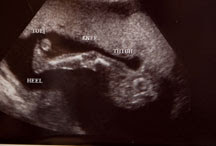

For those of you who haven’t had a baby ultra sounds probably mean absolutely nothing to you. I remember countless expecting friends emailing their ultra sound photos and almost being irritated by the gesture. I mean, really… you’re trying to tell me that’s his what?!? Well something magical happens when it’s yours. You’re given super powers to spot any and every detail the photo displays. I saw that he was a he before the doctor could point it out. Formerly the black and white blobs would have left me clueless. Anyway, for those of you who share my super powers… isn’t he the cutest!!!

Above was the angle we so eagerly awaited. At no time was their any doubt as to whether or not we would know the sex. I mean really, 10 months of not knowing… not happening!

His profile! OMG, that’s all I can say. You can see his 5 little (and healthy) fingers resting on top of his head.